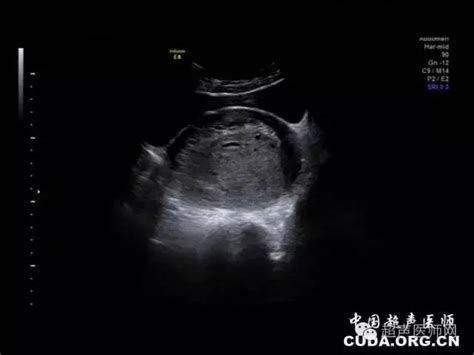

宫外孕就是指在受孕过程中,孕卵由于受到某些因素的影响而没能进入子宫腔以外着床发育,而是在子宫腔以外妊娠。宫外孕为妇科急症之一,患者属于治疗会直接威胁到生命安全。对于宫外孕的自查方法所有的育龄女性都应该有所掌握。

宫外孕的早期诊断主要是检测血HCG(绒毛膜促性腺激素)。因HCG是妊娠时所分泌的特异性激素,所以β-HCG可用于协助宫外孕早期未破裂的诊断。正常发育的绒毛所分泌的HCG量很大,每天的滴度不断的快速上升,每48小上升66%以上。即如果β-HCG每两天增加的量大于66%,可以诊断为宫内妊娠;而如果增加的量小于66%,则宫外孕或宫内孕发育不良的可能性很大。